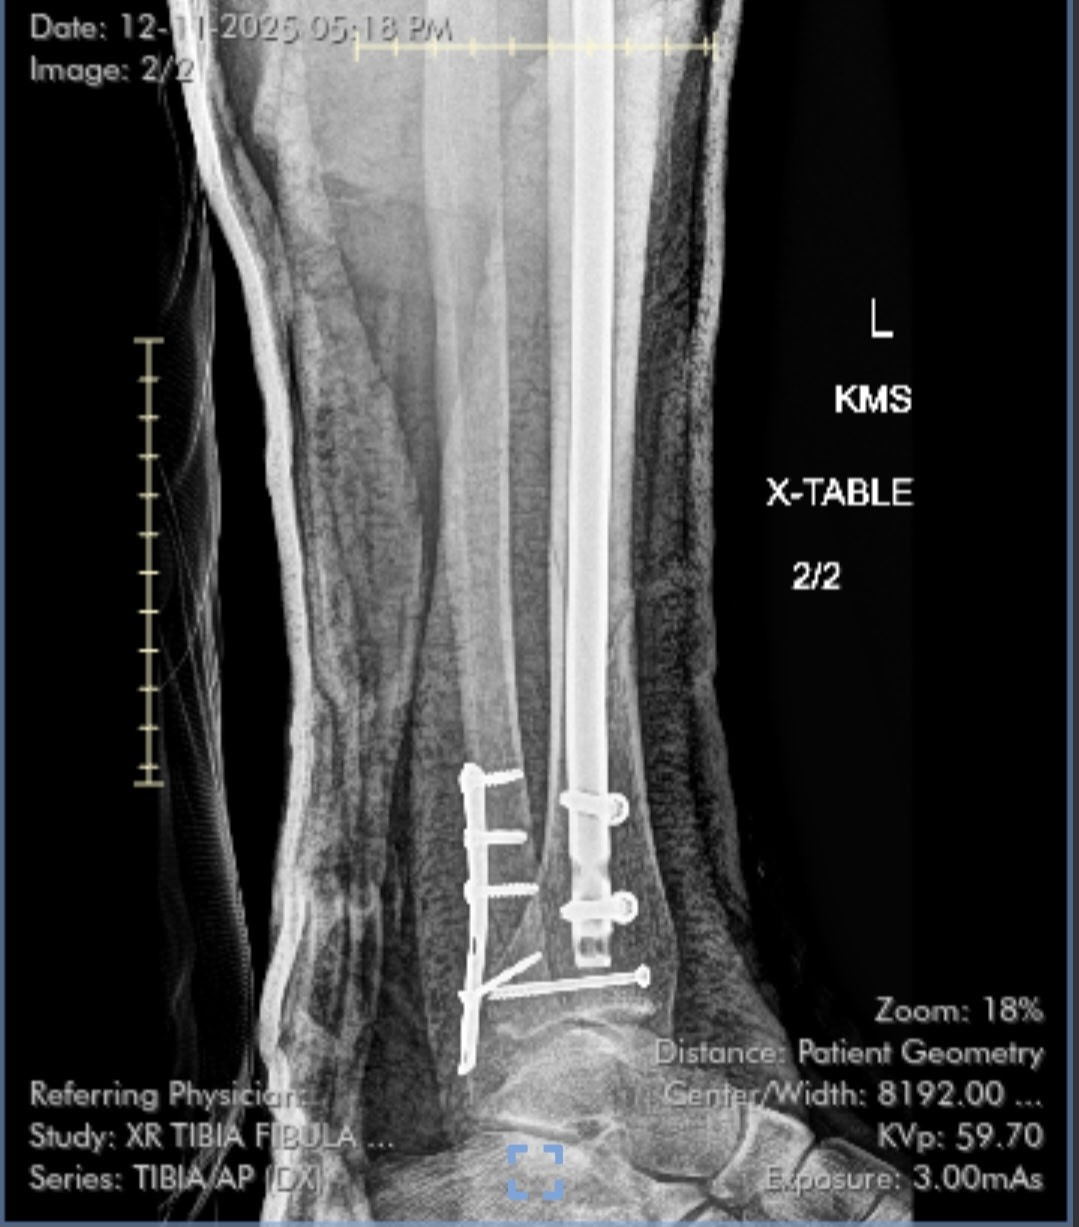

On December 3rd, our dear friend Chelsea was leaving her shift as a postpartum doula when she fell down the base of a narrow staircase at an overnight shift. The fall resulted in 4 breaks in her left leg, 3 of which were spiral fractures of her tibia and fibula. These required emergency trauma surgery and per her surgical team, she is now unable to bear any weight on her left side for at least 2 months. She will not be able to work during this time and she will need daily assistance for basic self-care at home– for example, using a commode, transferring to/from the hospital bed and wheelchair, meal prep, and more.